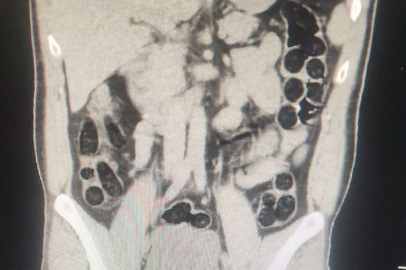

Batman Valiliğinden yapılan açıklamada, otobüs firmaları üzerinden yolcu olarak seyahat eden şahısların batı illerine yüklü miktarda uyuşturucu madde sevk edileceği bilgisi üzerine operasyon yapıldığı bildirildi. Operasyonda; otobüs ile seyahat eden 2 İran uyruklu şahsın yapılan kontrollerinde ve iç beden muayenesi sonucunda, şahıslardan birinin midesinde 76 paket halinde, 714 gram eroin maddesi ele geçirildiği belirtildi.

Olayla ilgili "Uyuşturucu veya Uyarıcı Madde İmal ve Ticareti" suçu çerçevesinde yakalanan 2 İran uyruklu şüphelinin, sevk edildikleri adli mercilerce tutuklanarak cezaevine teslim edildiği kaydedildi.